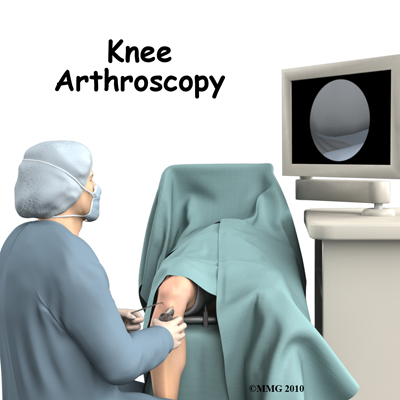

Knee Arthroscopy

The use of arthroscopy has revolutionized many different types of orthopedic surgery. During arthroscopy, a small video camera attached to a fiber-optic lens is inserted into the body to allow a physician or surgeon to see inside without making a large incision (arthro means joint, scopy means look). The knee was the first joint in which the arthroscope was commonly used to both diagnose problems and to perform surgical procedures inside a joint.